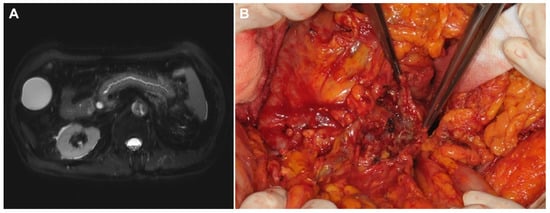

| No. | Age/Sex | Tumor Location | Cause of PAP | Severity | Preop. Max. Serum Amy/Lip (U/L) | Preop. Max. CRP (mg/dL) | Time to OP (days) | OP Name | Field Findings |

|---|---|---|---|---|---|---|---|---|---|

| 1 | 59/F | AoV | mass | Moderate | - | - | 45 | Exploration only | Adhesion around the pancreas Unable to approach pancreas |

| 2 | 58/M | Bile duct | ERCP | Severe | 527/921 | 0.07 | 90 | Total pancreatectomy | Severe necrotizing pancreatitis Hard to identify SMV |

| 3 | 72/F | Bile duct | ERCP | Mild | 1684/3827 | 9.54 | 7 | Total pancreatectomy | Necrotic change of the whole pancreas Unable to perform PJ anastomosis |

| 4 | 69/M | Bile duct | ERCP | Mod | 1260/3703 | 19.39 | 15 | Total pancreatectomy | Necrotic change of the whole pancreas Unable to perform PJ anastomosis |

| 5 | 77/M | Bile duct | mass | Mild | 100/382 | 0.92 | 20 | Exploration only | Necrotic change of the whole pancreas Bleeding tendency with friable tissue |

| 6 | 61/M | Pancreas | mass | Mild | 676/1713 | 8.63 | 19 | Total pancreatectomy | Necrotic change of the whole pancreas Unable to perform PJ anastomosis |